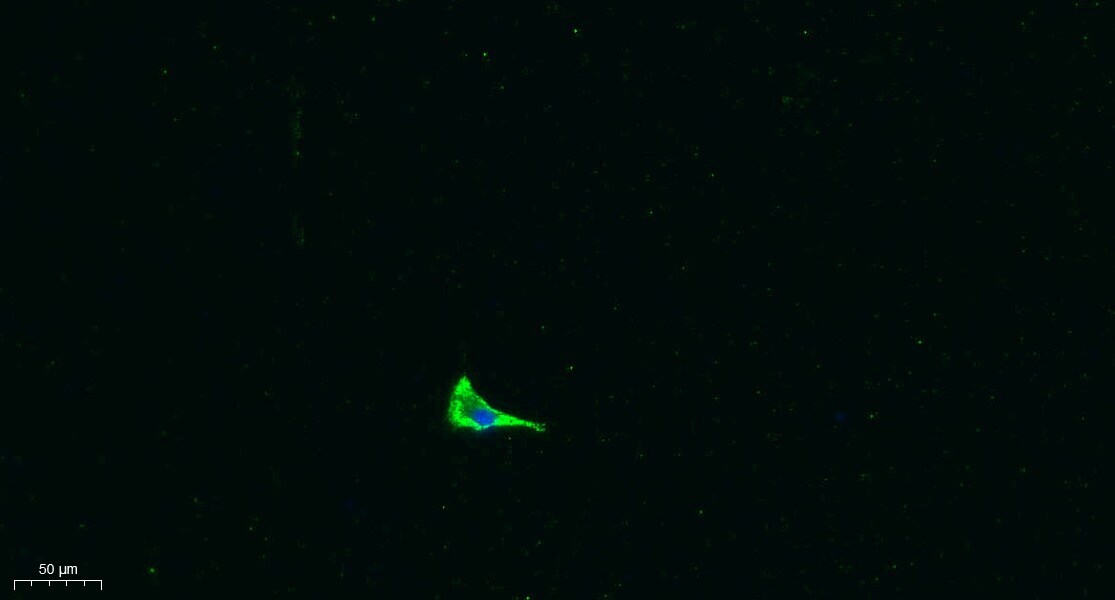

Supportive validation

- Submitted by

- Invitrogen Antibodies (provider)

- Main image

- Experimental details

- Immunocytochemical analysis of COL17A1 in A549.1 cells. The cells were incubated with COL17A1 Polyclonal Antibody (Product # PA5-67897) at a 1:200 dilution overnight at 4°C. An Alexa Fluor 488 conjugated Goat Anti Rabbit IgG (H&L) Antibody, diluted at 1:1000 (room temperature, 50 min) was used as the secondary antibody. Picture B: DAPI(blue) 10 min.